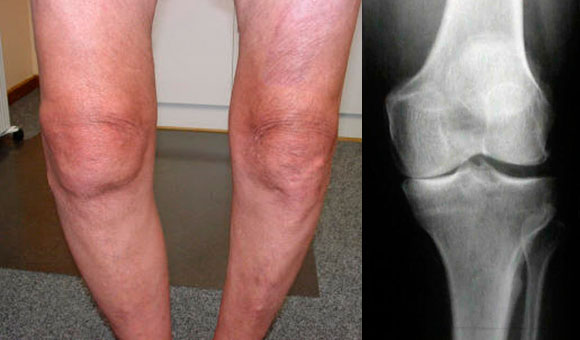

- При осмотре пораженного сустава можно заметить грубые контуры костей, формирующих колено.

- В запущенных случаях может наблюдаться контрактура сустава и искривление костей голени.

Первая степень гонартроза – пациент ощущает быструю утомляемость ноги и дискомфорт в области коленных суставов. При движении можно услышать хруст в колене, а также наблюдается небольшое ограничение подвижности. Форма коленного сустава сохраняет свои физиологические контуры, деформации не наблюдается. На рентгеновских снимках в прямой и боковой проекциях видно сужение суставной щели;

Вторая степень гонартроза – проявляется болевыми ощущениями в колене после длительной ходьбы или стояния на одном месте. Хруст в коленном суставе во время движения становится более заметным. Пациент испытывает трудности с полным сгибанием или разгибанием колена, возникают «стартовые боли». При проведении функциональных тестов врач фиксирует ограничение угла полного сгибания или разгибания коленного сустава. На рентгеновских снимках видно сужение суставной щели, а также участки разрастания остеофитов, края костей, формирующих сустав, становятся сплюснутыми;

Третья степень гонартроза – болевой синдром в коленном суставе становится постоянным. Колено отекает и ощущается горячим на ощупь. При наличии «суставной мыши» (осколков остеофитов) может возникнуть блокада сустава, проявляющаяся острой болью и невозможностью двигать коленом. Активные движения в колене либо отсутствуют, либо сильно ограничены. Изменяется физиологическая ось нижней конечности, что приводит к X-образному или O-образному искривлению ног. Коленные суставы деформируются, может возникнуть нестабильность колена.

На ранних этапах гонартроза рентгеновские снимки колена могут не выявить никаких изменений. Однако на более поздних стадиях заболевания можно наблюдать сужение суставной щели, отложение солей, повреждение костной ткани и склероз хрящевой структуры.